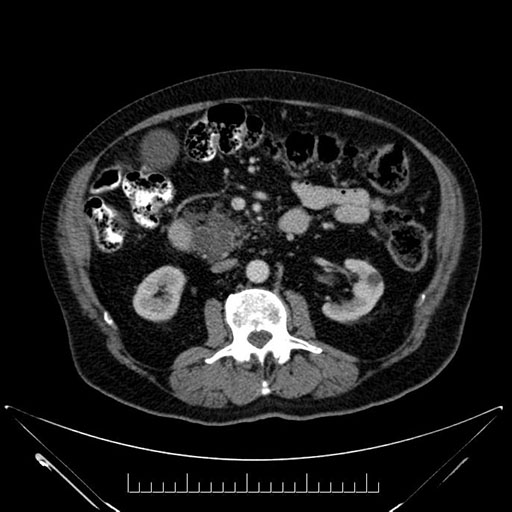

Axial - stented